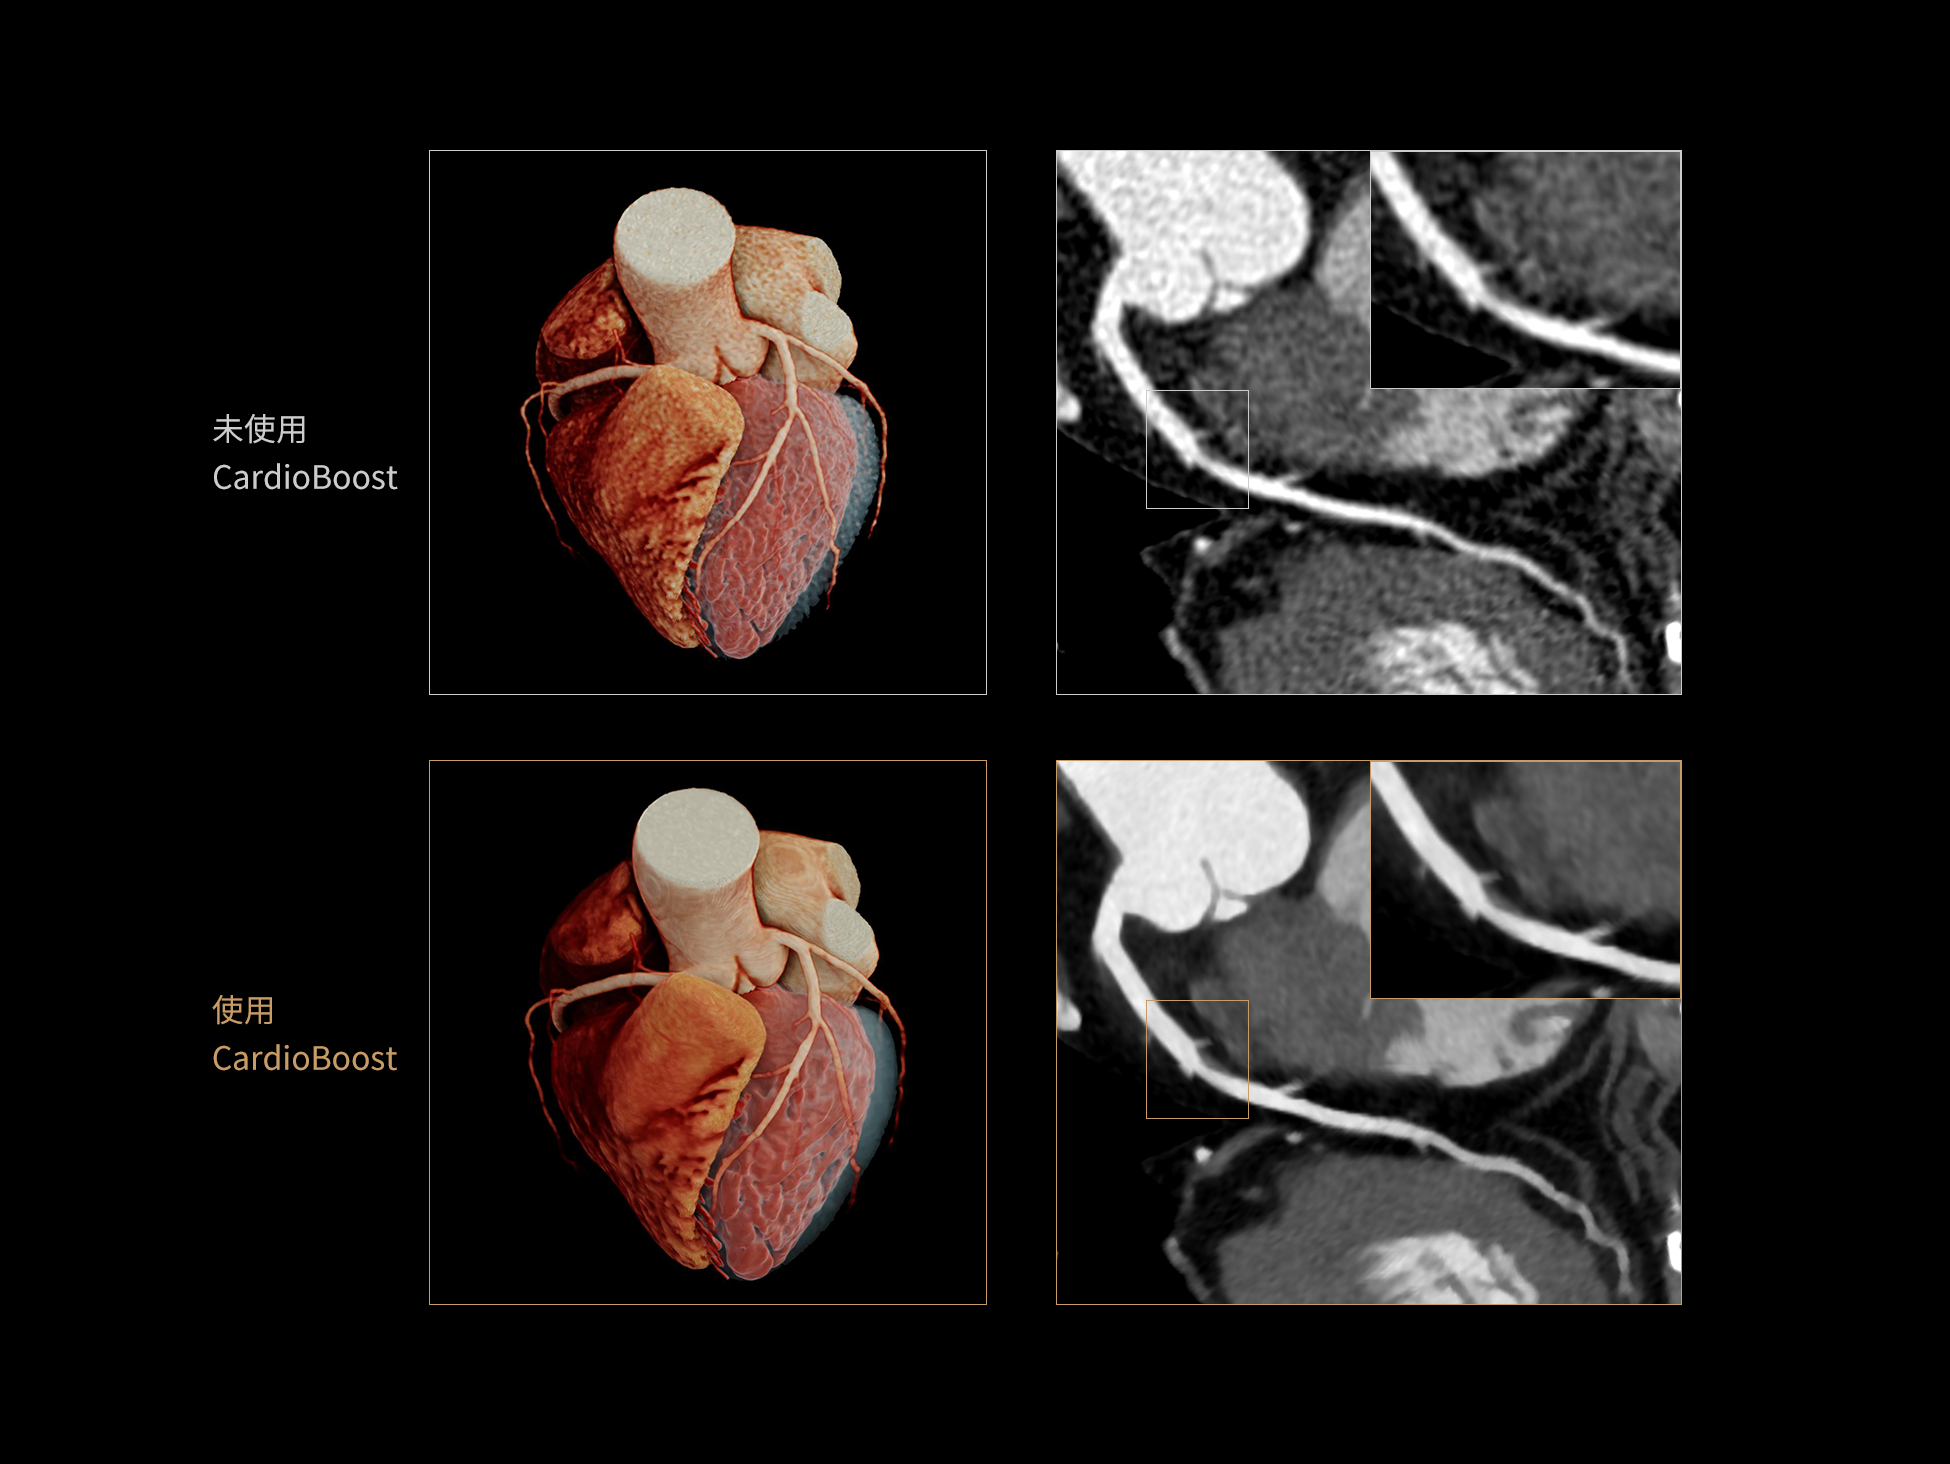

CardioBoost:专属网络设计,重塑心脏影像表现

目前心脏的 CT 检查还存在辐射剂量偏高、空间分辨率不足、 致密钙化伪影影响冠脉狭窄程度评估等方面的限 制[1][2]。CardioBoost 技术专为心脏 CT 高清成像而开发,通过 3D 神经网络的深度学习技术,利用先进的注意力机制在识别关键成像特征方面的出色表现,能够精确地聚焦于斑块、支架以及微小血管等关键细节,清晰展示这些结构与冠脉血管的边界,从而显著提高诊断的准确性,并提升医生的诊断信心。创新的 CardioBoost 心脏图像重建算法,不仅实现了图像清晰度的提升和伪影的去除,更能在减少辐射剂量的同时,保证心脏图像的高质量和图像纹理的自然。

CardioBoost核心创新

采用 3D 神经网络的空间结构优势与精细的组织分类能力,CardioBoost 技术优化了组织对比,高清展示血管斑块,使斑块与血管边缘的轮廓清晰可辨,提升斑块诊断与评估的精确性。

借助 3D 神经网络设计、空间注意力机制聚焦与特征强化作用,CardioBoost技术提升图像的空间分辨率,实现冠脉支架的高清成像,对支架形态与管腔通畅度的评估更精准。

CardioBoost 整合先进的 3D 神经网络和空间注意力机制,大幅增强数据处理的速度与精确度。该技术能有效抑制由致密钙化引起的晕状伪影,清晰展现钙化斑块的原始结构和大小,对冠脉狭窄的评估更加精确可靠。